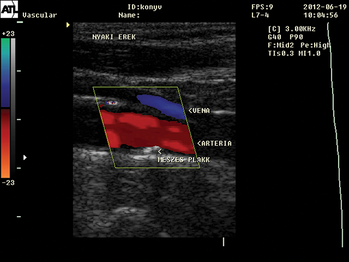

- Érbetegségek

- Az artériás és vénás megbetegedések érsebészeti vonatkozásai